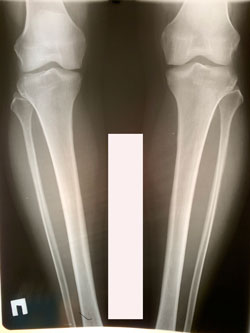

Исходник - 35 лет.

дата операции - 25.01.2021

Вложения

image-25-01-21-07-51-1.jpg

image-25-01-21-07-52.jpg